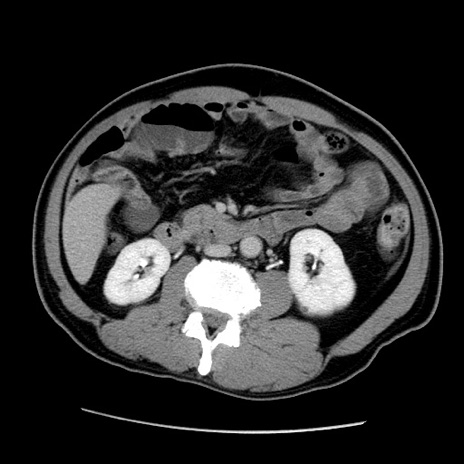

症例22(横断像)

【症例】50歳代男性

【主訴】腹痛

【現病歴】AVMからの被殻出血のため回復期リハ病棟入院中。 本日午後3時頃急に下腹部痛が出現した。

【既往歴】AVM、被殻出血、虫垂炎、高血圧

【身体所見】意識晴明、左半身不全麻痺、会話の理解は良好、36.5°C、腹部:膨隆、全体に板状硬、下腹部正中に圧痛点あり、反跳痛-、筋性防御不明、右下腹部にope scar

【データ】WBC 9400、CRP 0.06